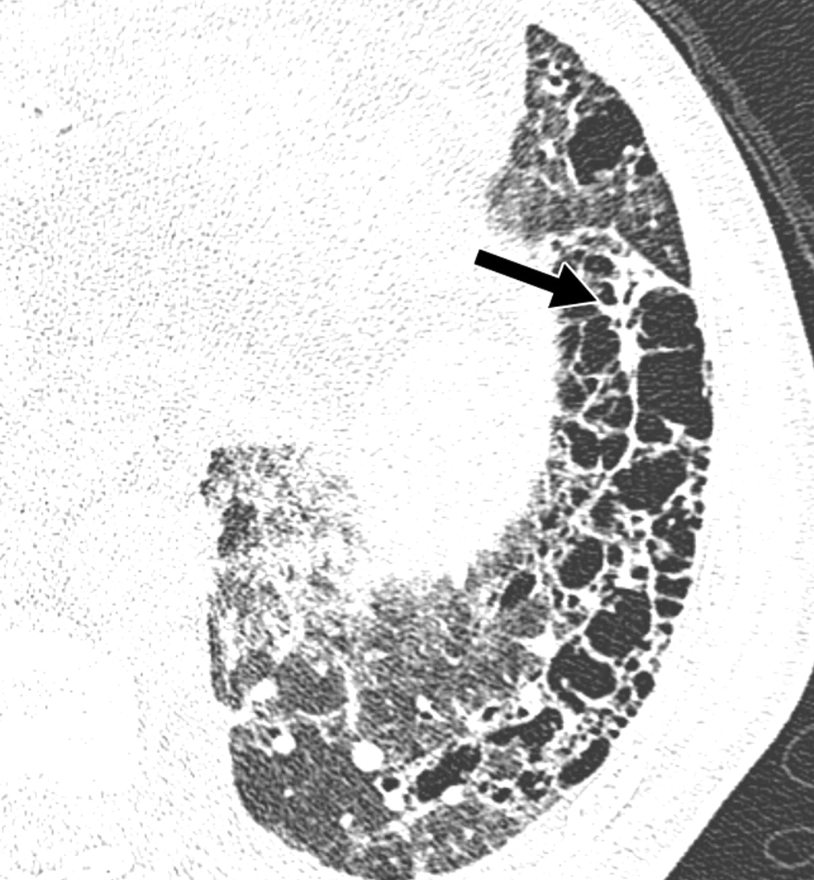

指導医 「間質性肺疾患の分類に重要なHRCTパターンをざっくり解説するぞ!」 専攻医 『今回は、特に特発性肺線維症(IPF)の診断で重要な UIPパターン の特徴についてっす』 指導医 「ちなみに、この分類は、病理学的なUIPが存在する確率を推測するためのものなんだ。 だから、スライドに示すUIPらしさを示す所見があれば、病理学的なUIPが存在する確率が高まるというわけ。 UIPらしさを示すポイントは、主にこの4つ。 🔹 蜂巣肺があるか? → 病理学的UIPを示唆する最も重要な所見 🔹 牽引性気管支拡張があるか? → 進行した線維化ではほぼ必発 🔹 分布はどうか? → UIPは 両側下葉・末梢優位 に分布するのが特徴 🔹 線維化のない部分が混在しているか? → UIPは 不均一な線維化分布 を示す これらがあると、病理学的なUIPを疑うぞ。 だから、HRCTを読むときは、こういった所見を慎重に評価するクセをつけようぜ! <つづく↓>